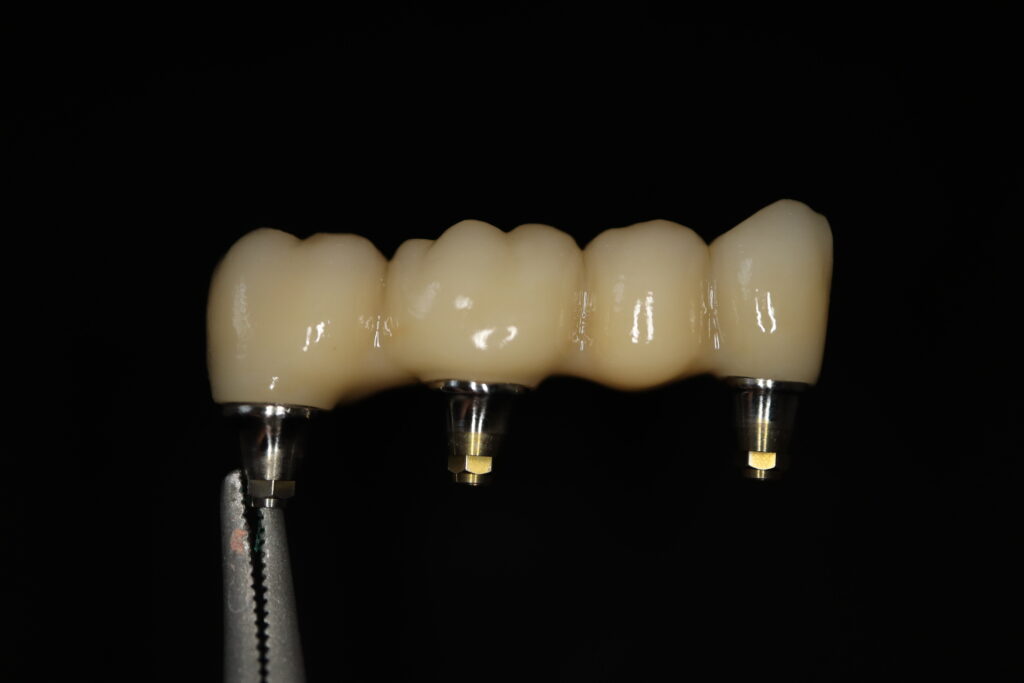

Спустя 27 дней был зафиксирован протез с опопрой на дентальные имплантаты из диоксида циркония с каркасом из титана.

Также на нижнюю челюсть был изготовлен мостовидный протез из 4х коронок (цирконий) с опорой на 3 индивидуальных абатмента с одной стороны и 1 коронка на иплантат с другой.